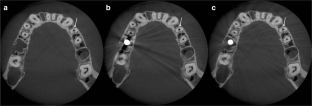

Fig. 1